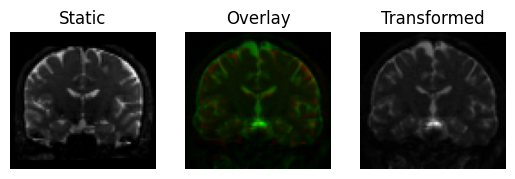

Now, let’s repeat this process with a simplified functional interface. This interface constructs a pipeline of operations from a given list of transformations.

pipeline = ["center_of_mass", "translation", "rigid", "affine"]

And then applies the transformations in the pipeline on the input (from left to right) with a call to an affine_registration function, which takes optional settings for things like the iterations, sigmas and factors. The pipeline must be a list of strings with one or more of the following transformations: center_of_mass, translation, rigid, rigid_isoscaling, rigid_scaling and affine.

xformed_img, reg_affine = affine_registration(

<Figure size 640x480 with 3 Axes>

Registration result with an affine transform, using functional interface.